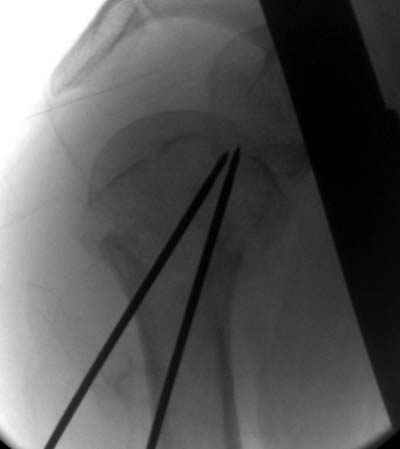

Здесь случай перелома-вывиха плеча, больному 56 лет, после "дважды" закрытой неудачной репозиции, опять же ургентно взяли в операционную, после полного общего обезболивания попытались сделать репозицию, и фиксацию провели спицами.

Больной находился в повязке, примерно напоминяющей косыночную, рекомендованы движения в локтевом суставе и маятниковые движения в плече, спицы удалены в три недели (были случаи миграции)

Да. У нас довольно скромный опыт такого остеосинтеза (по 2 случая - плечо и наружная лодыжка), дошли до использования самого простецкого троакара, через который мы сверлим кость и вводим 6 мм стержни, когда накладываем аппарат. Соответственно, в качестве забойника отлично работает любой стержень от аппарата Илизарова. Еще из наших туземных особенностей - страшная любовь к спицевым дистракторам, поэтому делали в нем. Результат у этой дамы неизвестен, т.к. она из области и уехала рожать сразу после остеосинтеза, сейчас прошло больше 5 месяцев...

Что-то, наверно, сделали мы не совсем оптимально, поскольку у Анатолия Федровича и его соратников как-то красивее "раскрываются" спицы в головке плеча - надеюсь, он прокомментирует и подскажет, что надо подправить.